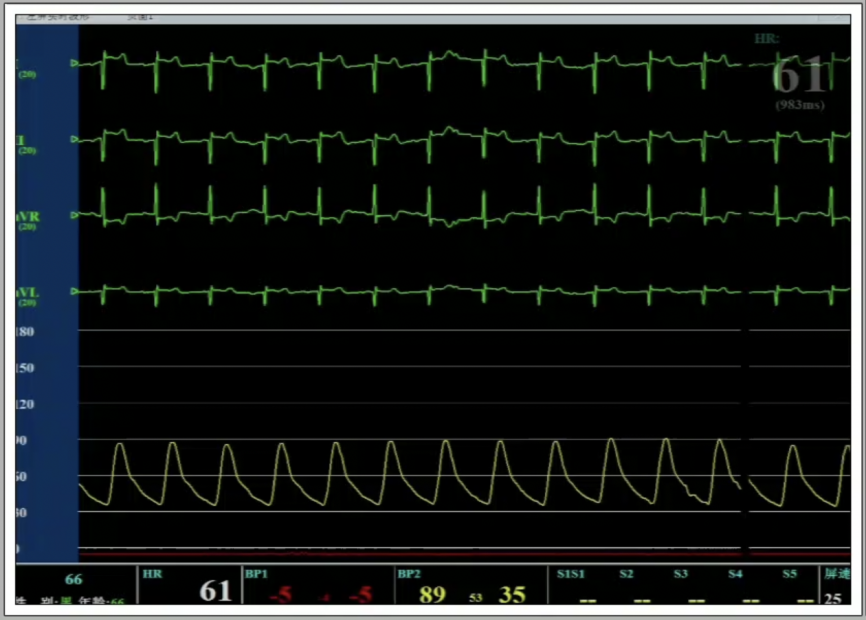

5、调整至共平面角度,瓣膜到位,快速起搏下精准释放瓣膜。

6、瓣膜植入且撤出导丝后,造影超声结果均显示瓣膜工作良好,术后导管测量压差8mmHg,经胸超声检测微量瓣周漏,手术成功。